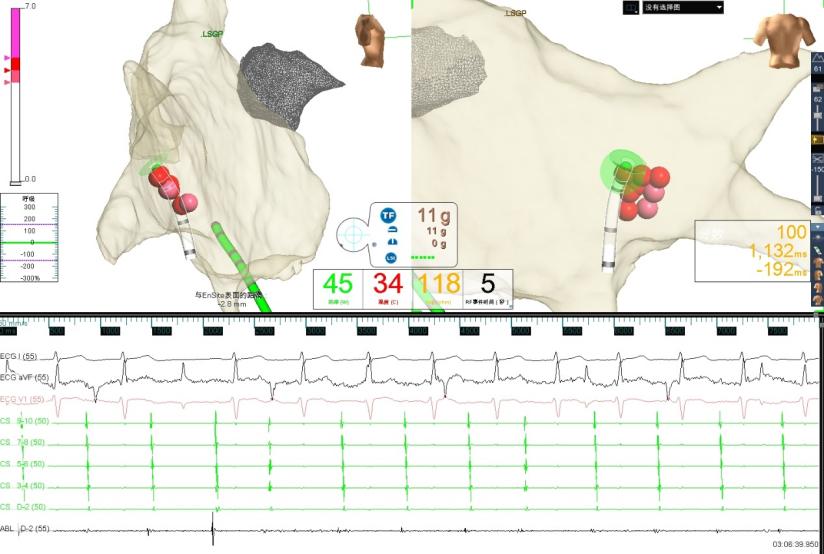

图2 消融右前GP时窦性心房频率增快,房室非1:1下传,心室率稍增快

图3 消融右下GP时房室传导恢复为1:1下传且心室率明显增快

图4 GP消融靶点

经与患方充分沟通治疗方案后,5月9日,在寿锡凌教授指导下,酉鹏华副主任医师、韩稳琦博士、赵永勇主治医师等为患者局麻下成功行经导管心脏迷走神经节消融改良术。术中先行心脏腔内电生理检查术,消融前测窦房结恢复时间(SNRT):1404ms,房室结文氏点(CSNRT):700ms,依次消融左房左上神经节丛(LSGP)、左房左下神经节丛(LIGP)、左肺静脉间神经节丛(MTGP)、左房右前神经节丛(RAGP)、左房右下神经节丛(RIGP),消融RAGP时窦性心房频率从40-46次/分提升至95-100次/分,但表现为房室传导阻滞,房室非1:1传导特点,心室率提升不明显,消融RIGP时房室结迷走张力减低,房室传导明显改善,房室呈1:1传导,心室频率提升至95-100次/分。